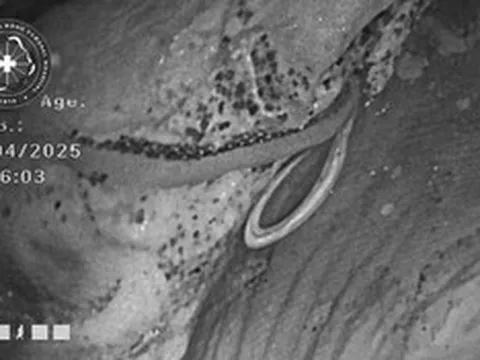

Khối u buồng trứng nặng 4,3kg được các bác sĩ lấy ra từ cơ thể bệnh nhi. Ảnh: BVCC.

Trong ca mổ, ê-kíp đã cắt bỏ hoàn toàn khối u buồng trứng phải nặng 4,3kg, đảm bảo lấy trọn khối u nguyên vẹn. Bệnh phẩm ghi nhận chứa nhiều thành phần như răng, tóc, xương và các tổ chức kém biệt hóa.